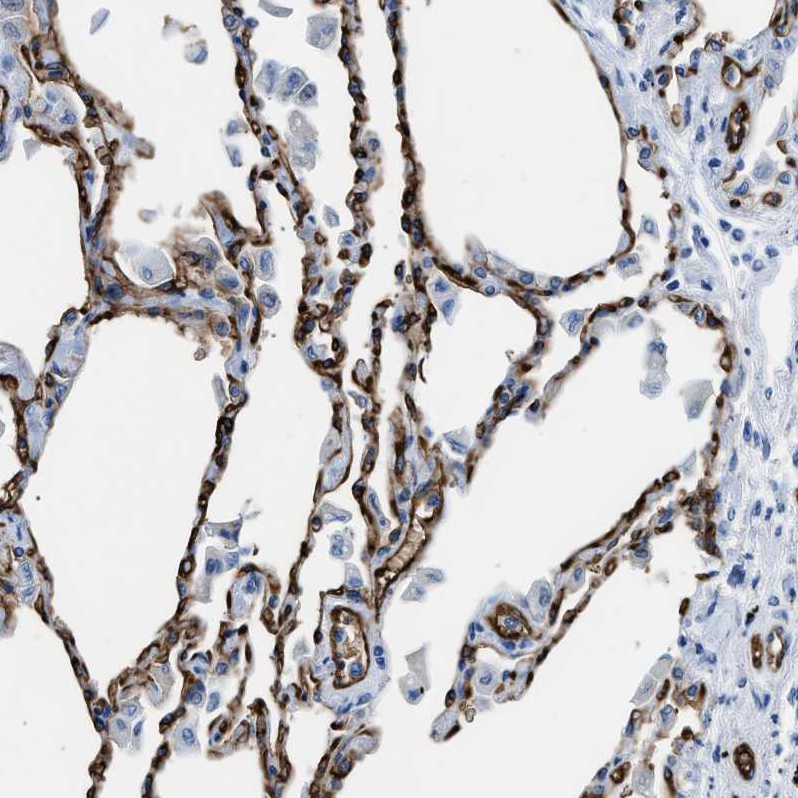

Immunohistochemistry analysis in human kidney and liver tissues using HPA019206 antibody. Corresponding AQP1 RNA-seq data are presented for the same tissues.